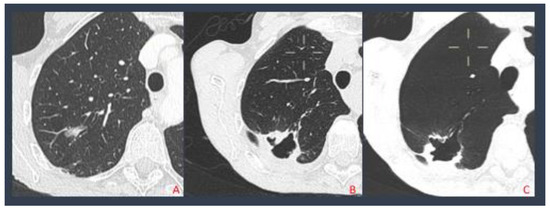

2.2.1. Standard CT-Guided Procedures

2.2.2. SIRIO-Guided Procedures